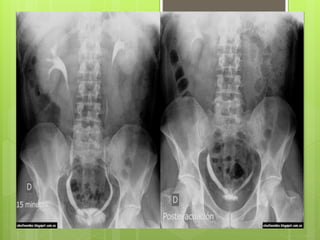

Radiografía a los 15 minutos

 Se pueden ver los cálices, la pelvis

renal y parte de los uréteres.

 Cuando un riñón es más opaco que

el otro, ésto obedece a persistencia

del material de contraste en el riñón

(nefrograma persistente) y sugiere

obstrucción del uréter.

 Ver trayecto ureteral y

desembocadura de los uréteres en

la vejiga